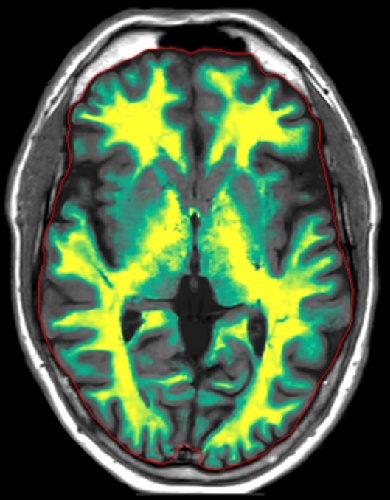

AI 再構成技術 SmartSpeed と定量 MR を組み合わせた Smart Quant Neuro は、1回の高速定量スキャンでマルチコントラスト画像と定量画像が得られ、診断の信頼性を向上させます。